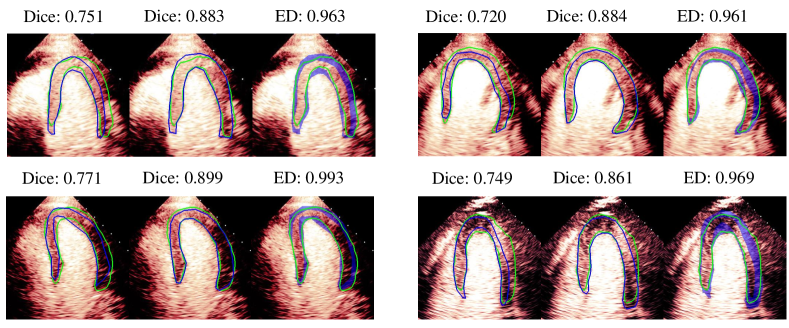

Visualization of myocardial segmentation from these methods is also shown in Fig. 4. We can see that for the Consensus, Confusion Matrix and Consistency methods, some unregulated shapes or discontinuity exist because the model cannot discriminate the actual myocardial from the artifacts which have the same intensity and texture information. However, the results of our method can alleviate the problem and accurately segment myocardium in MCE images.

In Fig. 6, we show the evaluation comparison of four images using Dice and extended Dice. Images in each group represent the Dice evaluated by cardiologist 2, Dice evaluated by cardiologist 5 and extended Dice. It can be seen that there exist large variations in Dice when using different cardiologists’ annotations as the ground truth, which may lead to misjudgment during evaluation. For example, we may think the segmentation quality is low (Dice0.77) based on the annotation from one of the cardiologists, but the quality is actually pretty good based on the annotation from another one (Dice0.86). However, using extended Dice will alleviate the problem because all these images are considered good (extended Dice0.96).